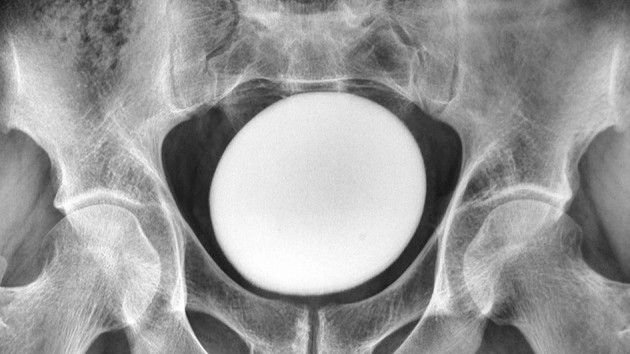

What happened next: When doctors conducted a physical examination of the man’s abdomen, they detected a large, smooth and solid mass above his pubis — the front of the pelvis where two pubic bones are connected by cartilage.

The dense mass wasn’t attached to the pelvic area or abdominal wall, and an ultrasound scan revealed that it was an egg-shaped object about 4.3 inches (11 centimeters) in diameter, according to a report of the man’s case.

The extracted stone weighed 1.8 pounds (826 grams) and measured about 5 inches (13 cm) long, 4 inches (10 cm) wide and 3 inches (8 cm) tall.